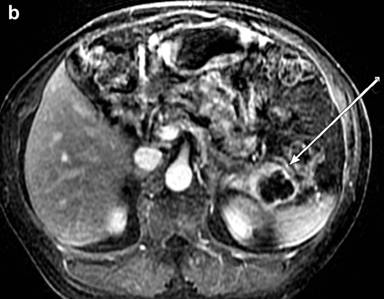

Medical image diagnosis by radiologists is based on their training, experience and individual judgment to visually identify key image features, which aid them in making decisions. Texture analysis is a wide range of methods incorporating image filtering techniques (wavelets, Gabor, grey level co-occurrence matrix, etc.) that can be used to describe variations in image intensity or patterns. Some of these patterns or differences might be imperceptible to the naked eye but texture analysis with statistical pattern recognition techniques can be used to evaluate texture pattern differences in images. A basic routinely used feature, for example, is size. Texture feature analysis of CT images has shown promise in pancreatic cancer [14]. Similarly, work has been done to identify features on FDG-PET images in other tumors, such as esophageal, [15]. Tuli et al. [7] found texture features of the FDG-PET images in a small sample of subjects that correlated with response to SBRT. By using this pilot data and incorporating knowledge gained from work in esophageal cancer, a prospective study would be helpful for further assessment. In addition, some centers routinely use MRI (Figure 1) for staging of pancreatic adenocarcinoma. Feature analysis of MRI images may hold more information [16]. Since gemcitabine interferes with DNA synthesis, MRI techniques like diffusion weighted imaging may be helpful since diffusion weighted imaging is affected by changes in cellular density.

|

Figure 1. A 76-year male with poorly differentiated ductal adenocarcinoma in the tail with perineural invasion and lymphovascular invasion on the resection specimen Total of 4/15 positive lymph nodes were found. Genetic testing was negative for EGFR, KRAS, and BRAF mutations. MRI before surgery shows: a. restricted diffusion on diffusion weighted imaging; b. little to no enhancement two minutes post-contrast injection. c. Follow-up FDG-PET-CT two months later showed multiple metastases in the liver with SUV up to 9.8. |